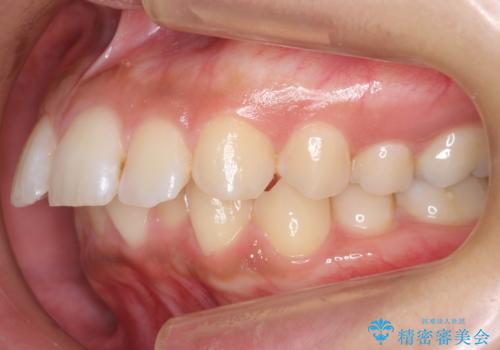

- 前歯を下げたいと来院。

初めは、上だけ抜歯しましたが、もう少し口元を下げたいとのことで追加で下顎を抜歯しました。

年齢の割に歯が動きにくかったこともあり、また、追加で抜歯して結果として時間がかかってしまいました。口元が大きく下がり、結果には満足していただけました。

横顔が大きく変わり、満足していただけました。